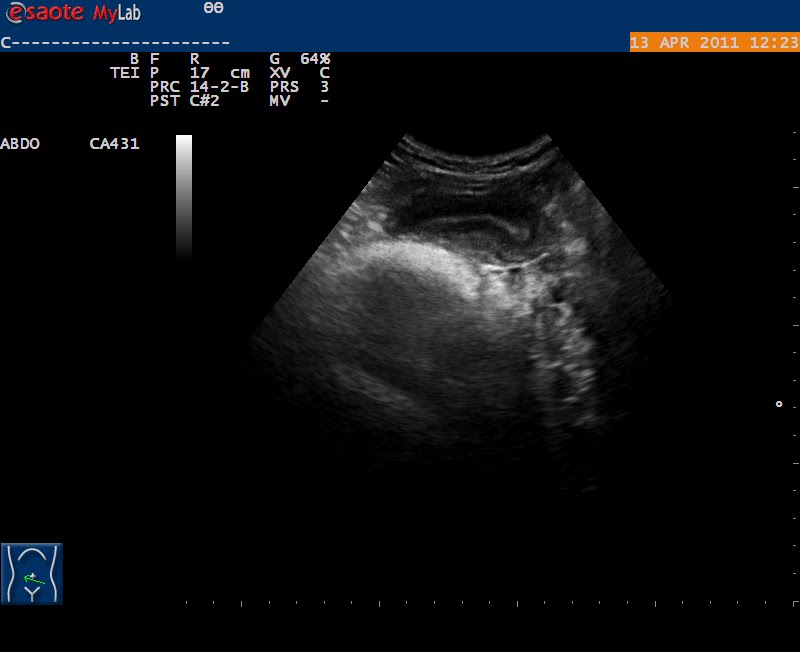

imagen ginecologica (?)

Hola amigos, os envio unas imagenes, de una mujer de 42 a. la primera hace 2 años, vista en ginecologia, y no digo dx, para no influir, las otras 2 actuales, ella esta asintomatica, espero vuestras opiniones . saludos